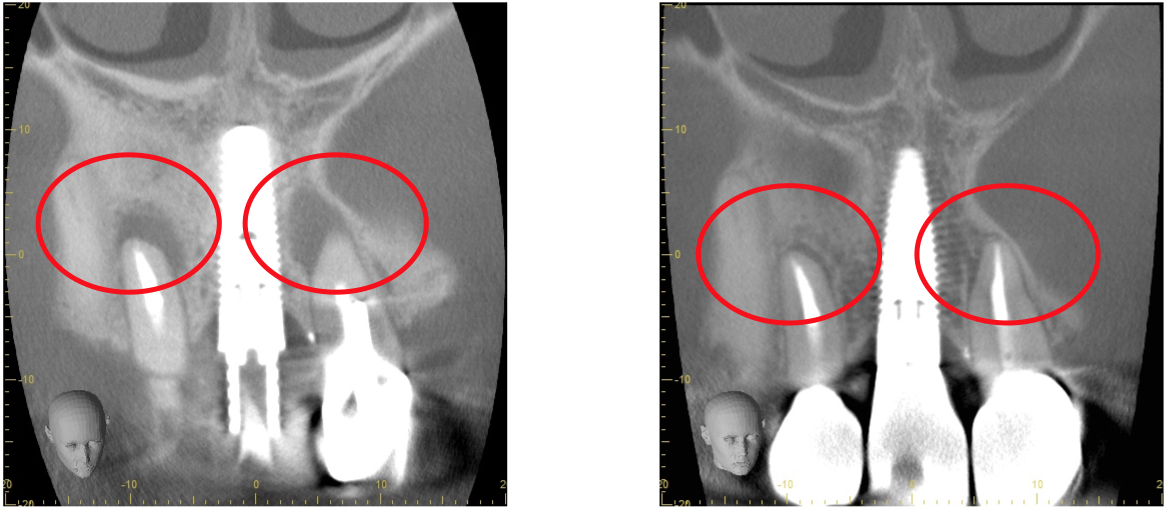

歯科用CTとは一般の医療用CTを歯科治療用に特化した装置です。

当院ではこの歯科用CTを使用して三次元で歯の構造を把握します。

任意の角度や位置から歯・顎骨を確認することもできるので治療の精度が大幅に向上します。

通常の根管治療を行っても症状が良くならない場合には外科的根管治療が必要となってきます。

歯根の外側に感染が及んでいる場合、通常の根管治療では感染源を除去することができないため、感染部位周辺の歯肉から感染源に直接アプローチする必要があります。